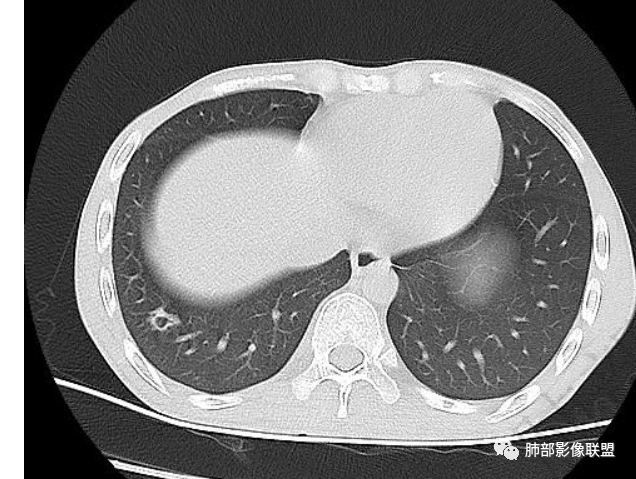

以下为2021-7-15日上腹部CT

影像与临床:1.青年男性,HlV阳性,颜面部皮疹(未提供皮疹图像)、发热(高热),实验室CRP、PCT高,T-Spot阴性。2.右肺下叶空洞结节,壁厚不均,边界清楚,其内线状影,未见液平及钙化,未见卫星灶,纵隔淋巴结增大,双侧腋窝见增大淋巴结。心腔内低密度提示贫血可能。肝脾影增大,未见结节影及块影。腹膜后见多发增大淋巴结。

综合分析:本例肺部影像学改变并不具有特征性,空洞性病灶须与多种疾病鉴别,但年轻HIV阳性患者,高热,皮疹,肝脾增大,纵隔、腋窝、腹膜后见多发增大淋巴结等都强烈提示马尔尼菲篮状菌感染的可能性。